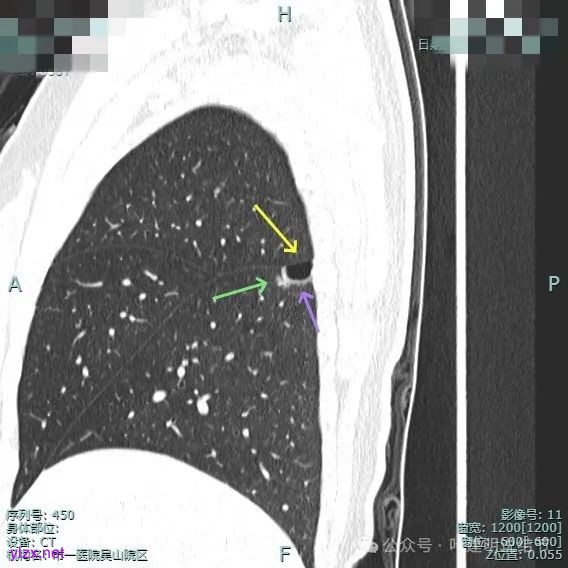

囊壁里面也有小空泡征。

混合密度但还是太致密,内壁毛糙不平。

病灶轮廓清楚,囊壁厚薄不均,贴着叶间裂与胸膜。